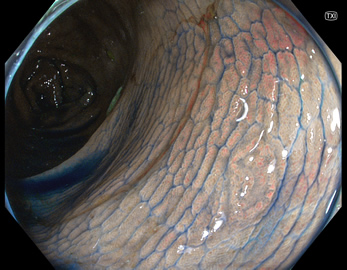

TXIは、「画像の構造を強調する」技術です。これは特別に目新しいものではありません。パソコンの画像編集ソフトや、スマホのアプリでも御馴染みの技術です。しかし、「どのような構造強調が実際に、内視鏡に一番、合うか?(強すぎると不自然になる!)」は、難しい(アナログ的な)課題です。オリンパス社は数タイプのTXIモードを用意しました。半年間の試行錯誤の末、今では下記のモードがベストと判断しました。そして今では「TXI無しの内視鏡は不要(フルタイムTXI)」というまで常用しています。

以下に実例を挙げます

写真だけ、見ると「言われてみるとTXIの方が認識しやすい。でも僅かの差」と感じるでしょうが、この「僅かの差」が、人間の脳での検出には大きな差になります。青い色素(インジゴ・カルミン)が非常に強調され、粘膜の凸凹が明瞭になるのが特徴です。

通常観察 TXIモード